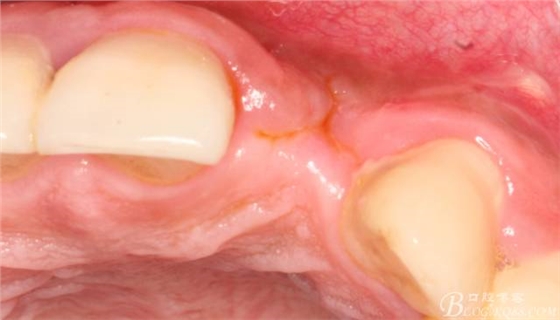

10天拆線一切正常,又過了兩周患者復(fù)診,自述期間無異常??趦?nèi)檢查,真的嚇了一跳,唇側(cè)鼓了個包,擠壓有白色分泌物溢出,絕對不是膿液,液體排除后,術(shù)區(qū)觸診空虛,外觀塌陷。這時候考研大夫的時刻到了,是先觀察一段時間再說?還是馬上進(jìn)行處理?我的回答是:馬上處理!如果你沒有及時處理,而是放患者回家觀察,那么接下來會發(fā)生如下情況:1.回家后患者家屬及親友會有很多你可以想象得到的討論;2.患者及家屬會對你產(chǎn)生不信任,勢必會到其他門診或醫(yī)院檢查,他院大夫會不會發(fā)表對你不利的言論;3甚至?xí)蚁嚓P(guān)法律界人士找你討要說法。